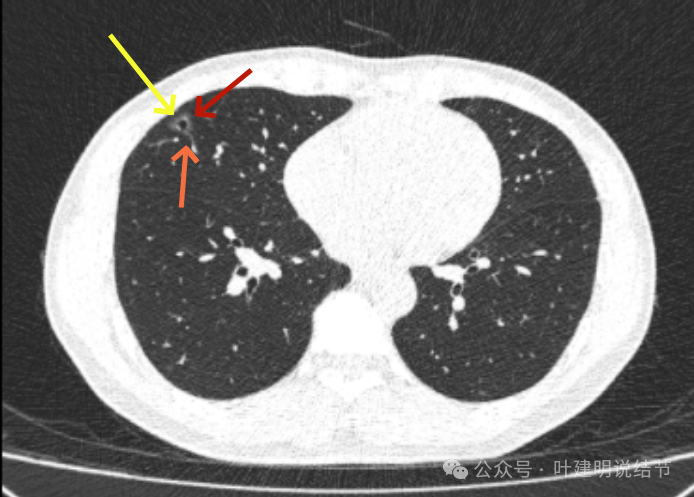

2017年初发现时,右中叶囊腔型病灶,囊壁密度淡但轮廓较清,有贴边血管,但血管无明显异常增粗,总体病灶较小,约1厘米光景或稍不到1厘米。整体轮廓是清楚的。